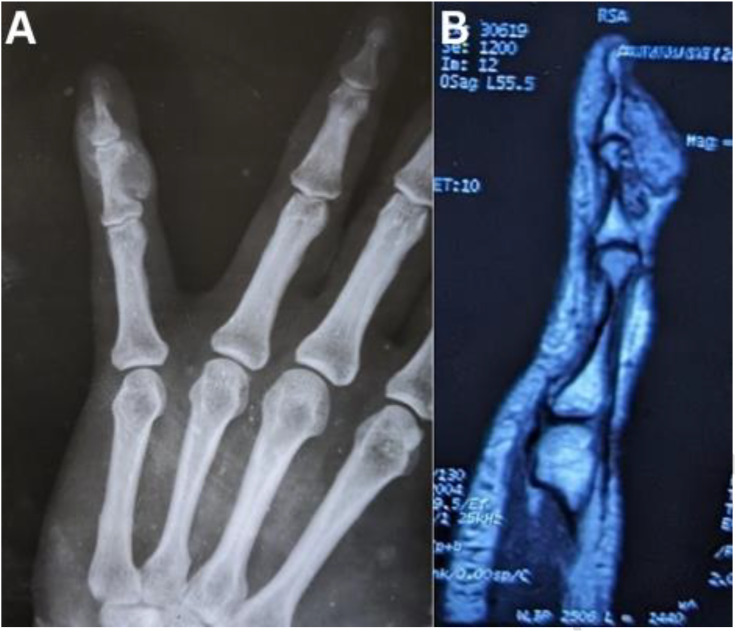

软骨黏液样纤维瘤(CMF)是一种罕见的良性干骺端骨肿瘤,其特征是软骨样、黏液样和纤维成分的结合。它可以影响任何年龄的任何骨骼,没有性别偏好。我们报告了一例47岁的女性CMF患者,她于2024年在印度加尔各答的一家三级保健医院出现左小指肿胀。影像学显示一分叶状病变,起源于左小指中指骨,延伸至远指骨基部。细针吸细胞学显示中度细胞黏液样病变。组织病理学检查仍然是诊断的关键,显示一个分叶状肿瘤,具有梭形到星状细胞区,与细胞间隙丰富的粘液样和软骨样基质相关。治疗包括完全切除无肿瘤边缘,因为局部刮除可能发生复发。

Chondromyxoid fibroma (CMF) is a rare, benign metaphyseal bone tumour characterised by a combination of chondroid, myxoid, and fibrous elements. It can affect any bone at any age, with no gender predilection. We report a case of CMF in a 47-year-old female patient who presented with swelling of the left little finger at a tertiary care hospital in Kolkata, India, in 2024. Imaging revealed a lobulated lesion originating from the middle phalanx of the left little finger, extending to involve the base of the distal phalanx. Fine needle aspiration cytology indicated a moderately cellular myxoid lesion. Histopathology, which remains crucial for diagnosis, showed a lobulated tumour with zones of spindle to stellate cells, associated with an abundant myxoid and chondroid matrix in the intercellular spaces. Treatment involves complete local excision with tumour-free margins, as recurrence may occur with local curettage.